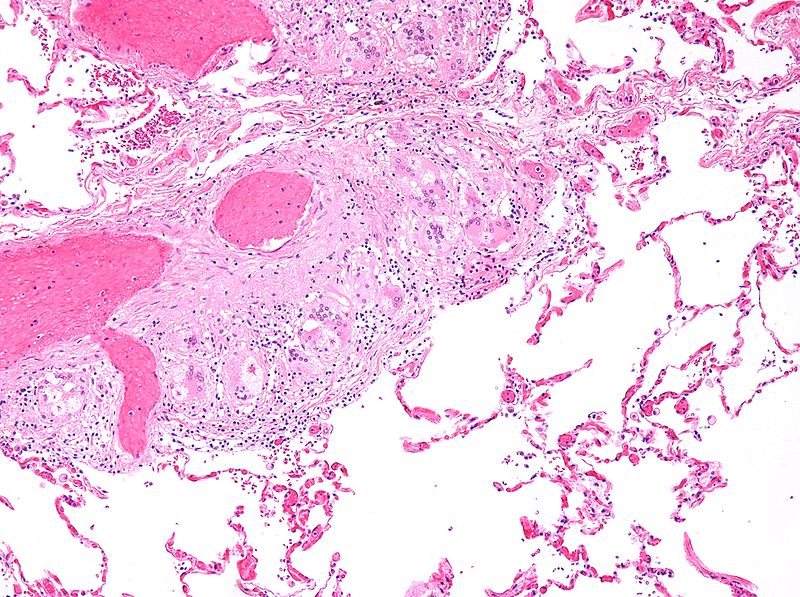

Histology of sarcoidosis includes naked granulomas and stellate inclusions (‘asteroid bodies’) are often seen within giant cells of the granulomas.